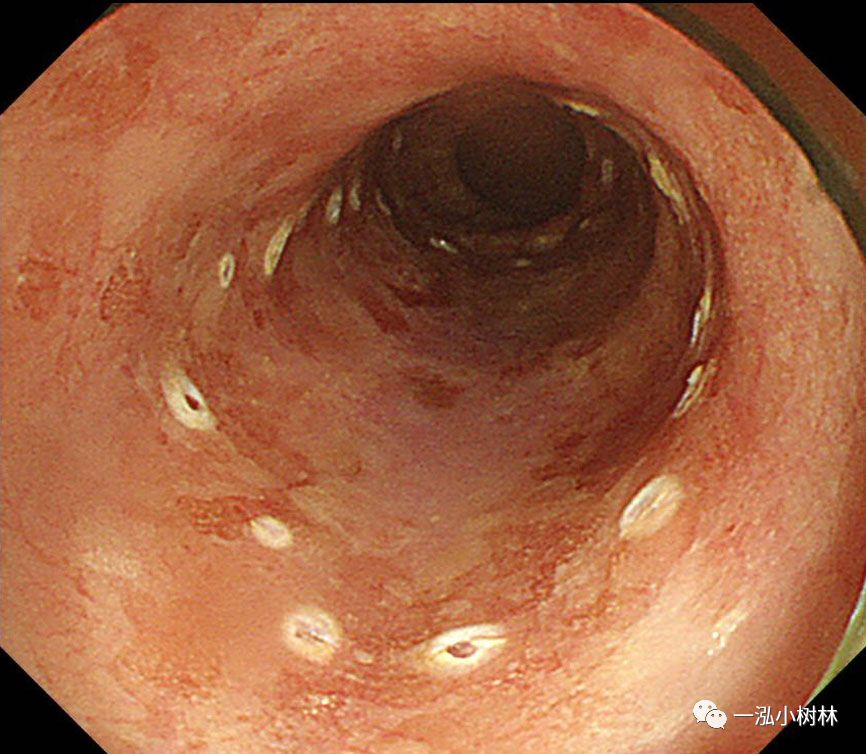

图3 碘染色:病变呈不规则拒染区